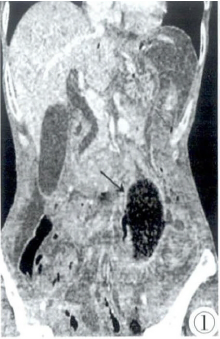

图1,2 CT增强冠状位(图1)及轴位(图2)示空肠近端见5 cm×5 cm×10 cm大小团块影,边界清,其内呈蜂窝状或筛孔状混杂密度及多发气泡影,增强未见明显强化,考虑粪石。其近段十二指肠未见扩张(胃肠减压后)。腹腔见散在小气泡,提示胃肠道穿孔。腹、盆腔见少量积液。